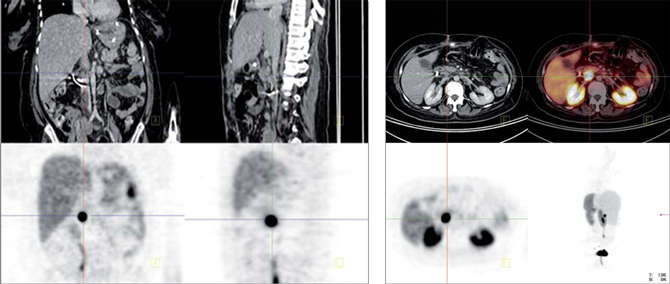

Insulinoma

Es un tumor endocrino del páncreas muy poco frecuente, se calcula su incidencia anual en 0,5-3 casos por millón de habitantes. Casi siempre está ubicado en el páncreas (1/3 en la cabeza, 1/3 en el cuerpo y 1/3 en la cola) aunque puede tener localizaciones ectópicas: duodeno, divertículo de Meckel, vía biliar, ovario y omento. Generalmente son pequeños: 40% son menores de 1 cm y 50% entre 1 y 5 cm y generalmente solitarios. Menos del 10% son múltiples, en cuyo caso debe descartarse síndrome de NEM tipo 1. Menos del 10% son malignos y 5% se presentan con metástasis, generalmente en el hígado o adenopatías regionales27 (Figura 10). Los insulinomas benignos y malignos suelen expresar receptores de somatostatina, el más frecuente es el subtipo 4 (80-90% de los casos), de moderada (10-50%) a gran intensidad (> 50% de las células tumorales) en los estudios inmunohistoquímicos. Los subtipos 1, 2 y 3 se expresan esporádicamente (40-50% de los casos) en los insulinomas benignos y malignos,generalmente en menos del 10% de las células neoplásicas. Los insulinomas benignos no expresan sstr 5 mientras que algunos malignos sí lo hacen28. Estos hallazgos están en línea con la experiencia clínica: aproximadamente el 50% de los insulinomas son positivos en la cintigrafía con pentatreotide y el tratamiento con radiopéptidos análogos de somatostatina (Lu177-DOTATATE o Y90-DOTATOC) es paliativo y sirve para ayudar al control de la hipoglicemia de estos enfermos29 (Figura 11).

Fusión SPECT/RM. Imágenes transaxiales de RM y SPECT con In111- pentatreotide.

Paciente con insulinoma metastásico. Se demuestra intensa sobreexpresión de receptores de somatostatina en metástasis hepáticas múltiples.